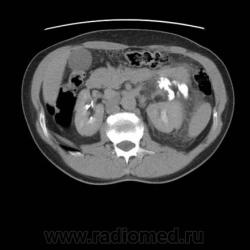

Травма. Боли в области поясницы.

Травматическое повреждение левой, по всей видимости, лоханки с разрывом и затеками контрастного препарата и мочи...